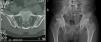

(a) CT scan of sacroiliac joints, axial section: fusion of the sacroiliac joints in the lower 2/3 due to bilateral ankylosis and bilateral sclerosis of the upper 1/3. (b) Hip X-ray, anteroposterior projection: complete fusion of sacroiliac joints, the coxofemoral joint relationships and in the pubic symphysis are preserved, decreased bone density.

The patient was evaluated by rheumatology ruling out rheumatoid arthritis and considering that he might have a psoriatic arthritis with mixed component: sacroiliitis and symmetric polyarthritis, due to the presence of early commitment of sacroiliac joints for the first one and subsequently cervical involvement, as well as of the hands, knees and feet for the second. VDRL, ELISA for HIV, antibodies against hepatitis B, and ANA were performed which were negative, and liver and renal profile which were normal, albumin/globulin ratio of 0.4 compatible with malnutrition. With the above, management with methotrexate (MTX) 15mg/week was started. Three months later, in an outpatient control, a slight improvement was observed, and therefore the dose of MTX was increased to 20mg/week. A month later, the patient was considered a candidate for management with a biological agent given the persistence of the joint symptomatology and the skin lesions. A PPD test was requested, which was negative (0) and treatment with infliximab 200mg/week 0, 2, 6 and then every 8 weeks together with MTX 15mg/week was started. Two months later it was evident an improvement of the skin lesions, reduction of joint pain and great improvement of the range of motion of the joints, allowing the patient to walk again. One year later there was a reactivation of the cutaneous disease, so the dose of infliximab was increased to 300mg/8 weeks and the dose of MTX was reduced to 12.5mg/week. Since then the doses of MTX had been progressively decreased until reaching 7.5mg/week. 10 years have passed and the patient has a stable clinical picture, including a PASI of 0 (Figs. 1b, 2b, 3b) and almost total recovery of his movements, being able to be self-sufficient in his daily life and needing only a walking stick since the bone damage presented was not reversed with the treatment (Fig. 5b and 6b). The above, despite the fact that the current conditions of the healthcare system to which the patient is affiliated do not allow the timely application of the medication.